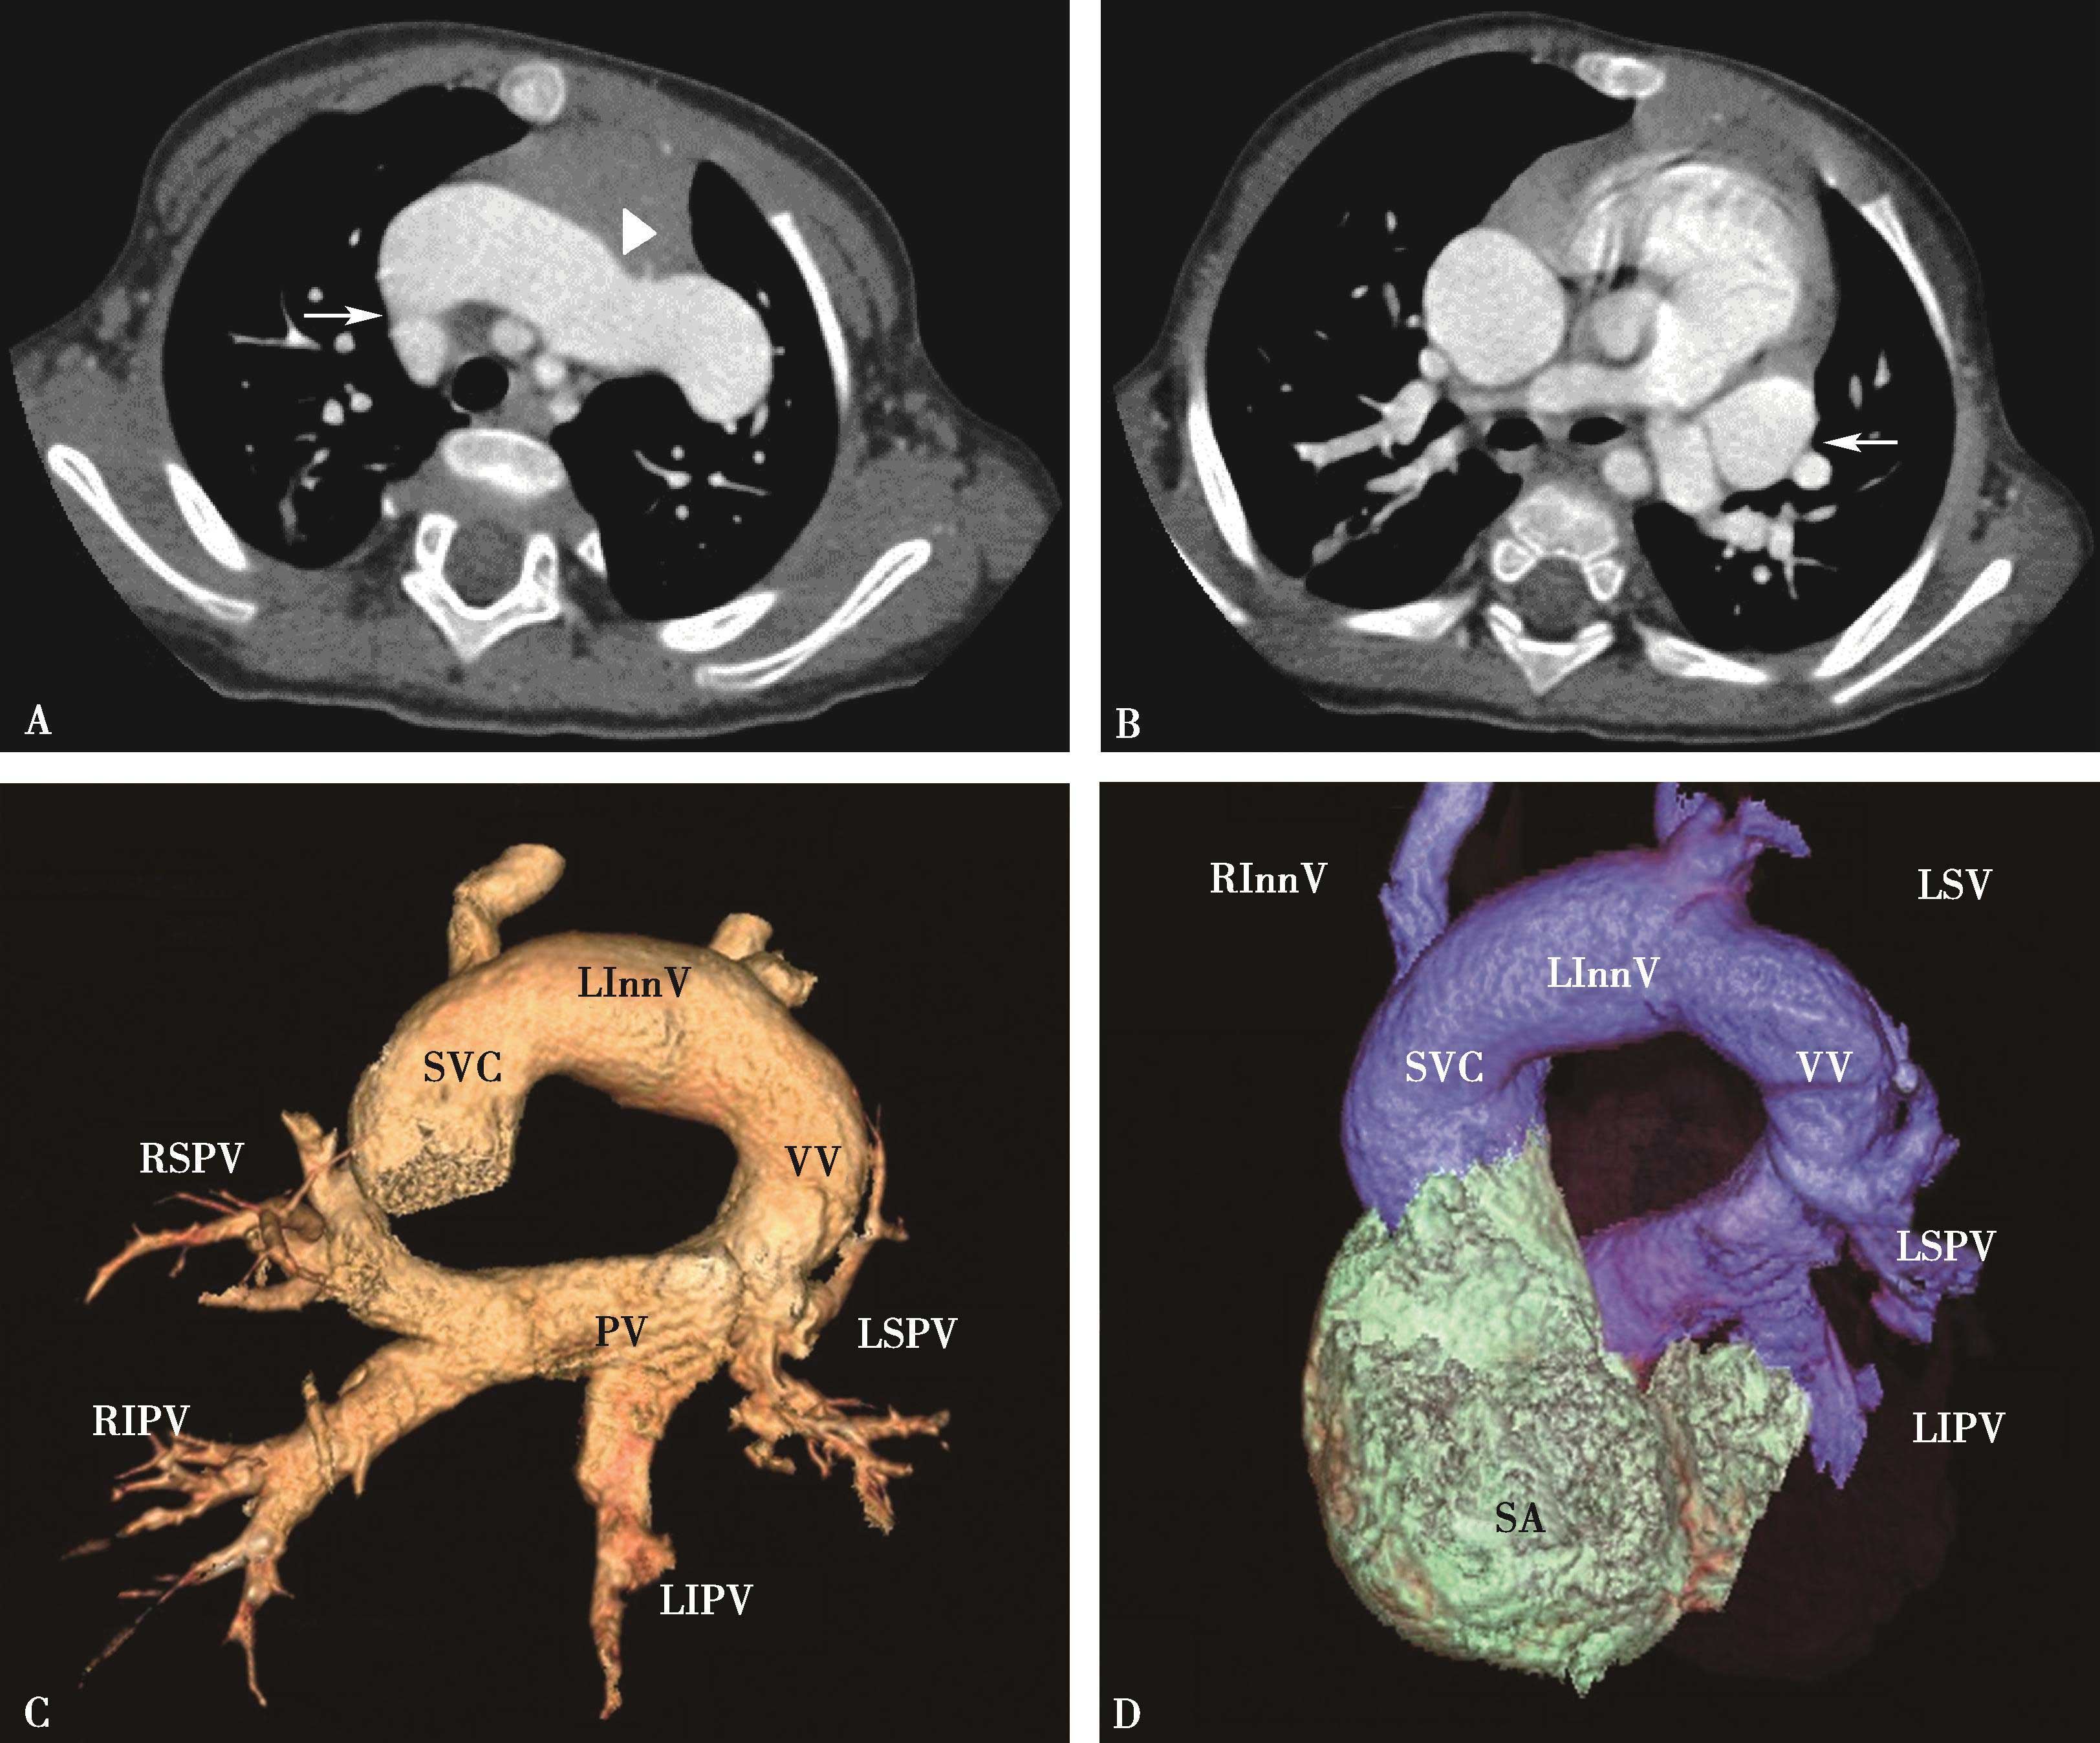

5.一期扫描 当ROI的CT值达到阈值时启动增强扫描程序。第一期扫描得到完整的肺静脉-左心房图像。如果达到诊断目的,可结束扫描(图8-1-11)。

图8-1-11 肺静脉CTA检查

A.上肺静脉(↑);B.下肺静脉(↑);C.肺静脉最大密度投影。LSPV:左上肺静脉;LIPV:左下肺静脉;RSPV:右上肺静脉;RIPV:右下肺静脉